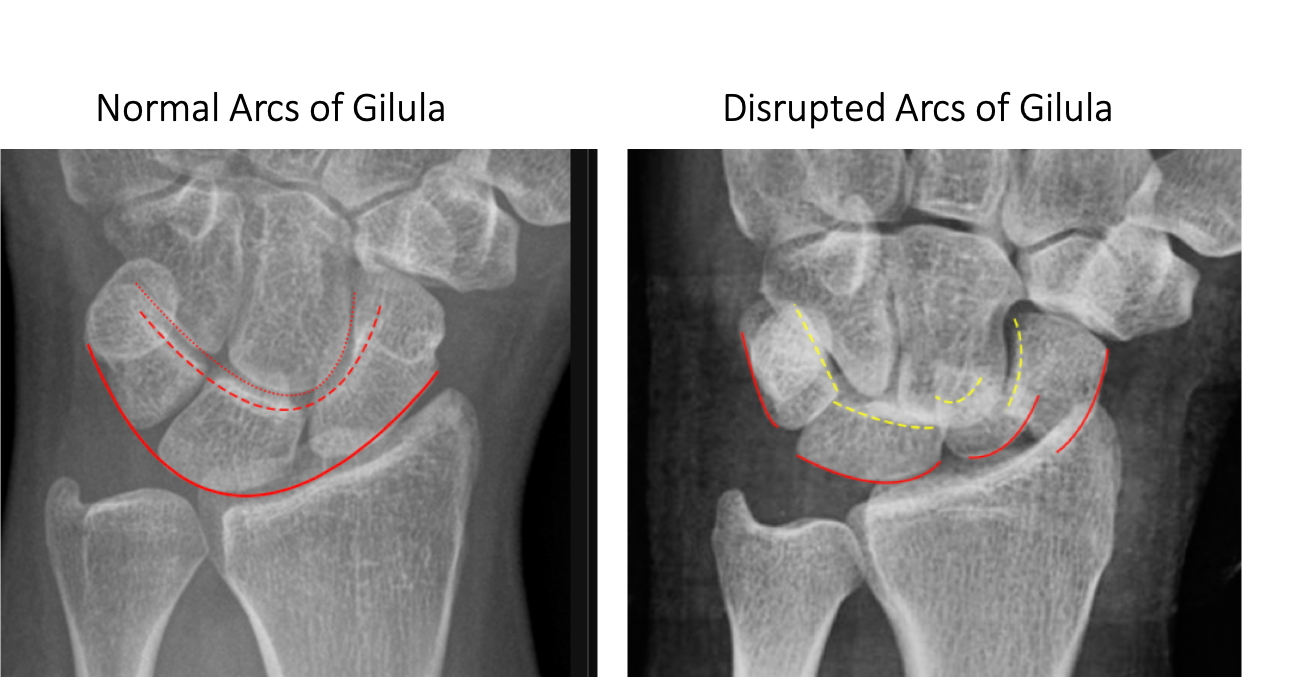

What are where are the arcs of Gilula?

Arcs of Gilula are U shaped arcs along the carpal bones. Disruption indicates ligamentous injury or fracture at the site of the broken arc. (the exception to this are congenital variants such as type II lunate morphology)

There are 3: